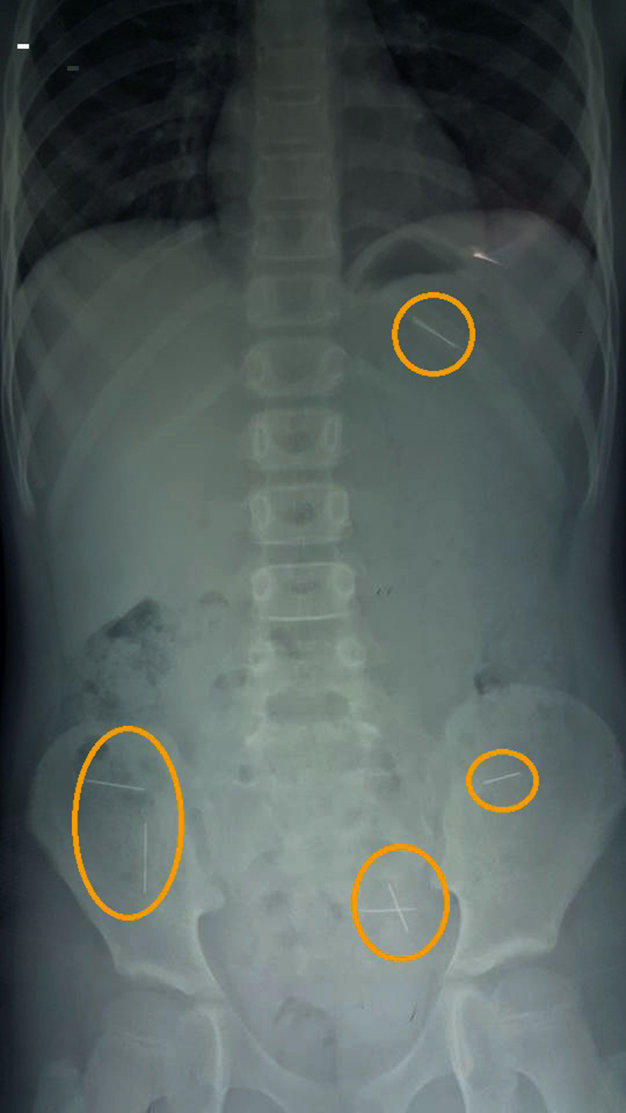

| Phim chụp X quang cho thấy những chiếc kim trong ổ bụng bệnh nhân (được khoanh tròn màu vàng) |

Kết quả chụp phim X quang, các bác sĩ đã phát hiện có bảy chiếc kim khâu trong ổ bụng bé gái.

Các bác sĩ cho biết may mắn cho bệnh nhân là những chiếc kim chưa gây tổn thương cơ quan nào trong ổ bụng, nên vẫn để những chiếc kim đi ra theo đường tự nhiên, và tiếp tục theo dõi.